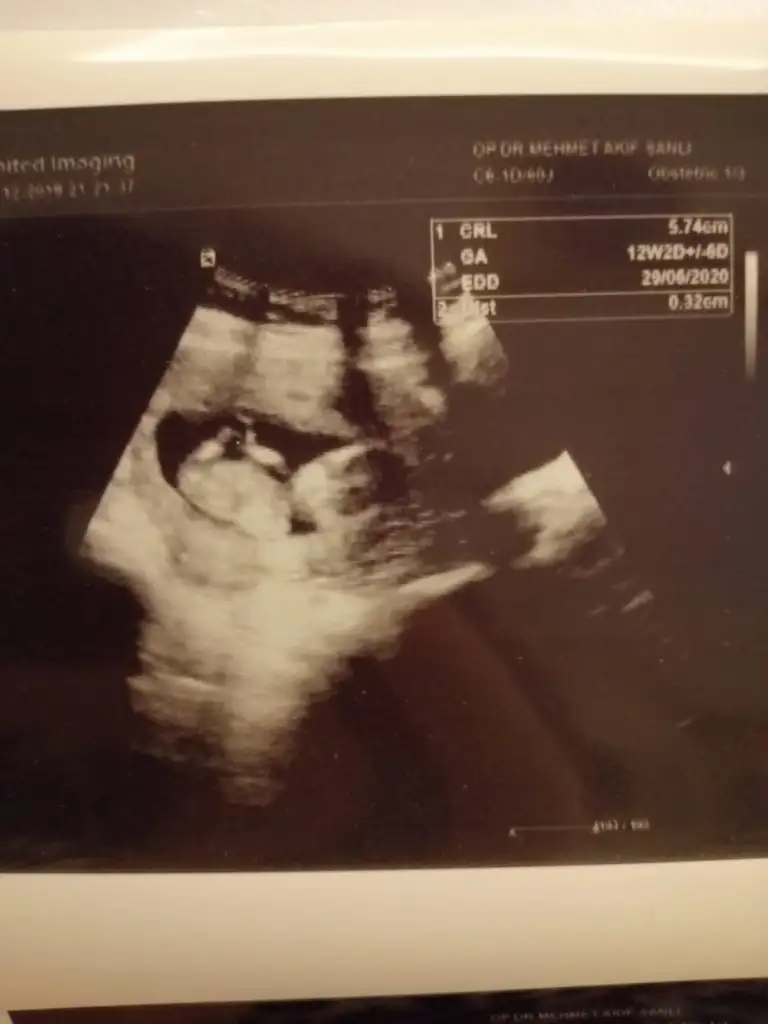

Ikra meyra Ikra meyra canım burda 12+2 ultrasona göre. Tekrar gönder demiştin var mı acaba bi şansım bu sefer 😂

Eklentiler

• IMG-20191218-WA0017.webp

IMG-20191218-WA0017.webp

14,8 KB · Görüntüleme: 89

• IMG-20191218-WA0018.webp

IMG-20191218-WA0018.webp

15,9 KB · Görüntüleme: 100